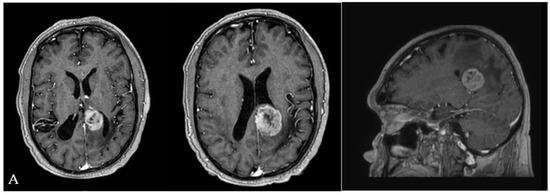

- Illustrative case n.1 (Case n.2 in the table, Figure 4)

Figure 4. (A) Pre-operative MRI showing a left-sided partially cystic lesion localized in the atrium and partially involving the temporal horn. (B) Intraoperative photograph propaedeutic for videoclip orientation. (C) Postoperative MRI showing complete tumor removal.

A 65-year-old female with a clinical history characterized by a slow and progressive reduction of the visual field and chronic headaches came to our attention because of an episode of seizure. A brain MRI showed a left-sided partially cystic lesion localized in the atrium and partially involving the temporal horn. Upon neurological examination, she was observed to have a lateral homonymous hemianopsia. She had normal motor strength in all extremities and no speech disturbances. She was right-handed. The patient underwent surgical removal of the lesion through IITA. Once the interhemispheric window was gained and the parieto-occipital sulcus identified, a 1 cm corticotomy perpendicular to the deepest end of the sulcus and adjacent to the cingulum was performed. Once the atrial cavity was entered, the lesion was identified. Its consistency was very hard. A patient and delicate dissection of the lesion from the surrounding ventricular ependyma was performed by the wise use of suction devices, bipolar forceps, and micro-dissectors. Once the tumor/brain interface was identified all around the lesion’s circumference, the lesion itself was separated into two pieces through the use of the Malis bipolar forceps. The biggest part of the tumor was removed by gently completing the dissection from the surrounding ependyma. Removal of the remnant portion was obtained by repeating the maneuvers used for the biggest portion.

The postoperative course was uneventful. The patient was admitted to the neurocritical care unit, where she was monitored for 24 h. The patient experienced a significant improvement of the visual field disturbances documented by campimetry, and her headache slowly recovered. At a 3-year follow-up, no seizures had been documented. Histological examination showed a choroid plexus papilloma.